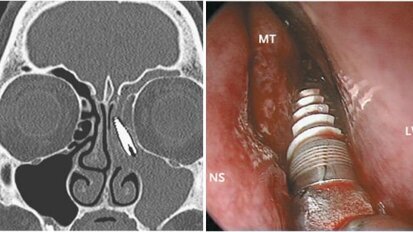

Zobozdravniki so podvrženi vizualni iluziji

Lismore , Avstralija : Da predmeti v ogledalu izgledajo bolj oddaljeni, kot so v resnici, je pogosta iluzija, s katero se dnevno srečujejo vozniki ...